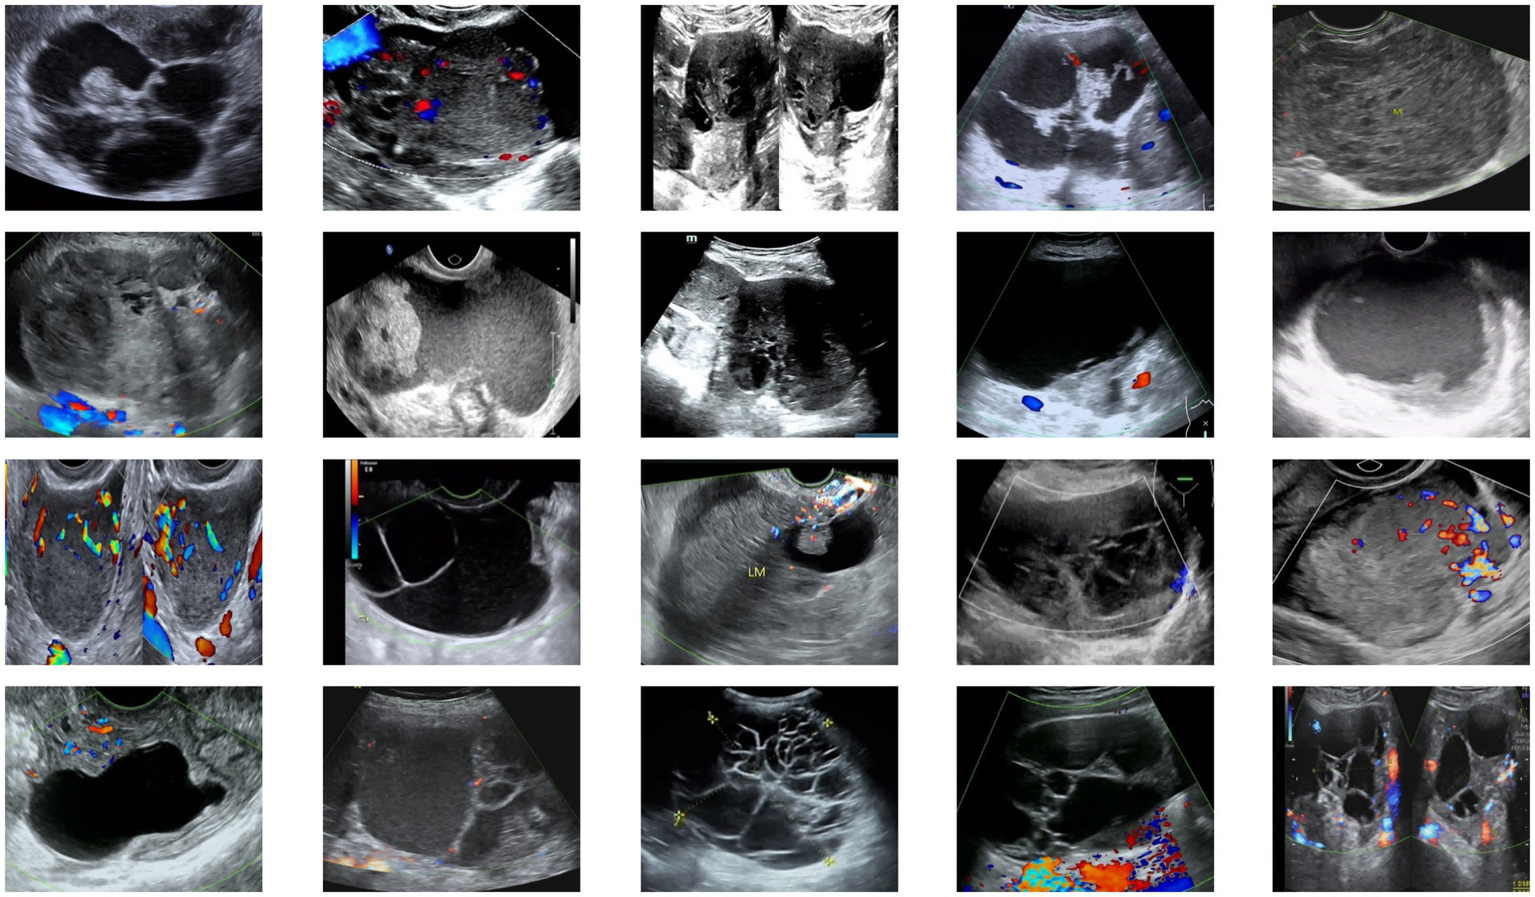

All images were annotated and verified by two professional physicians, with labels including tumor size, morphology, boundaries, and precise locations to ensure annotation quality and consistency. Annotated images were paired with corresponding label files and resized to a uniform input dimension of (512, 512, 3). To address data scarcity, augmentation techniques including horizontal flipping, affine transformation, and contrast enhancement were applied, expanding the dataset to 2,000 images. The data were partitioned into training and test sets at an 8:2 ratio to ensure generalization capability. Example images from the dataset are shown in Figure 5.

Figure 5

Examples from the ovarian tumor ultrasound dataset.